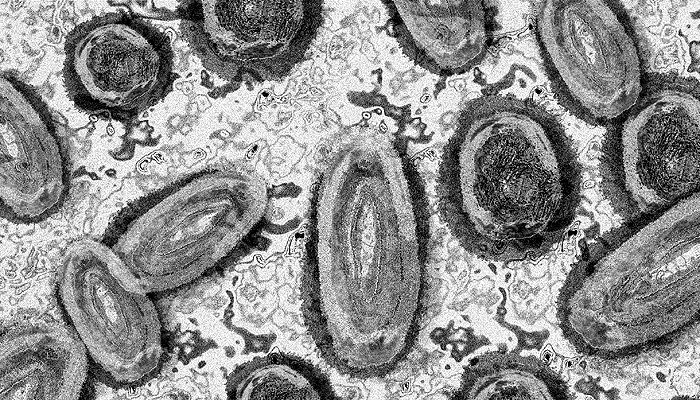

Waspada Cacar Monyet, Kenali Penularan dan Cara Menghindarinya Ilustrasi, cacar monyet. (Geralt/Pixabay)